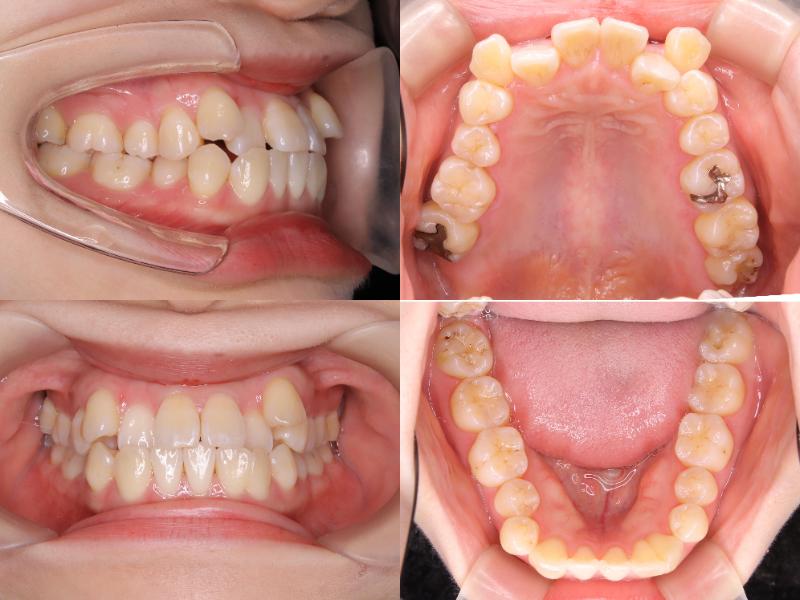

初診時年齢25歳1ヵ月の患者様です。

口元の突出感を主訴にご来院されました。

過蓋咬合と左上7番の根尖性歯周炎が認められたため、通常であれば上下左右4番を抜歯しますが、上下左右5番が処置歯であったため、5番を抜歯しました。